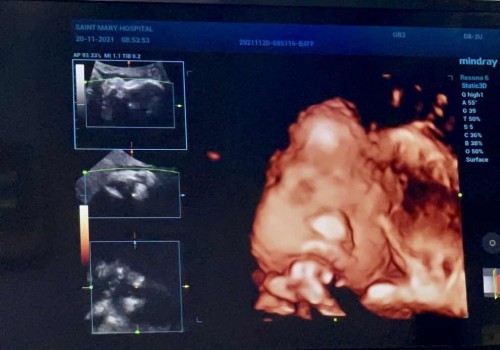

คุณแม่ท่านไหนมีปัญหาน้ำหนักน้องน้อยไหมคะ ตอนนี้คุณแม่เป็นกังวลมากเลยค่ะท้อง 33week น้องน้ำหนักแค่1700เองค่ะ มีวิธีเพิ่มน้ำหนักน้องบ้างไหมค่ะ